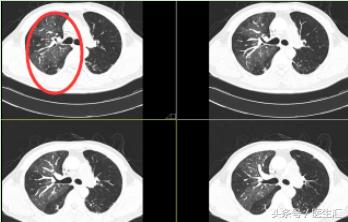

CT 图片示:

患者右肺肺野密度不对称,左肺尚可,出现的是 “马赛克征”。可考虑:小气道病变或肺栓塞。

P.S :“马赛克”征是肺小气道病变时高分辨力CT或薄层CT所示的一种非特异性征象。表现为肺密度不均匀,补丁状的异常透光区+斑片状的磨玻璃密度影镶嵌存在,形似“马赛克”。